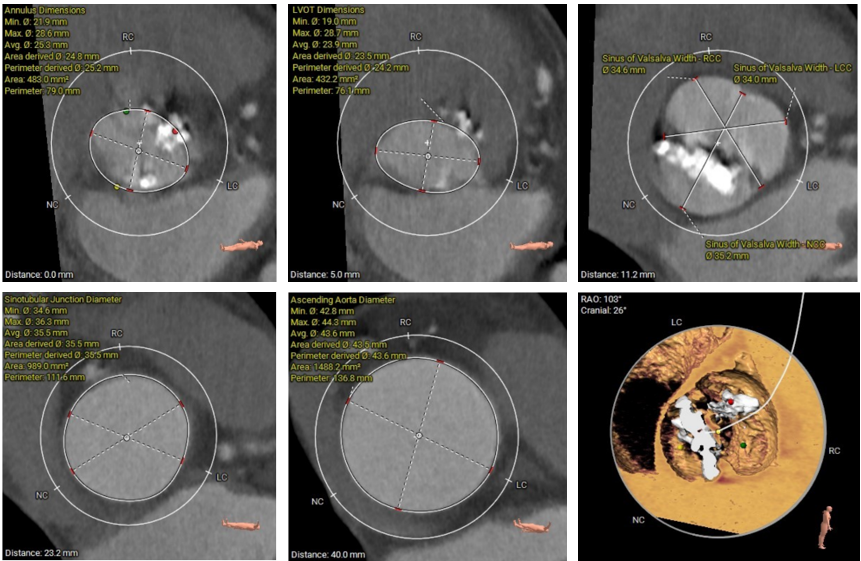

主动脉根部测量

瓣上结构测量

冠脉阻挡风险、左室大小及横位心评估

外周血管入路评估